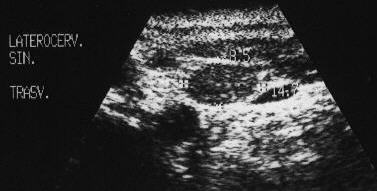

LeZiUni granulomatoAse

Loja laterocervicala dreapta.

Loja laterocervicala stanga

Femeie 31 ani. Leziuni hipoecogene, neomogene laterocervical bilateral. Tiroidectomie totala pentru neoplasm papilar cu extensie extracapsulara si metastaze linfonodale (T4 N1 M0) in urma cu 2 ani. Terapia radiometabolica.

Examen citologic: celule epiteliale gigante ca in granulomul

de corp strain; fibroza cronica granulomatoasa supurativa. Tireoglobulina din lichidul

de lavaj: nedozabil.

Aceeasi pacienta – fara semnal de vascularizatie

interna.